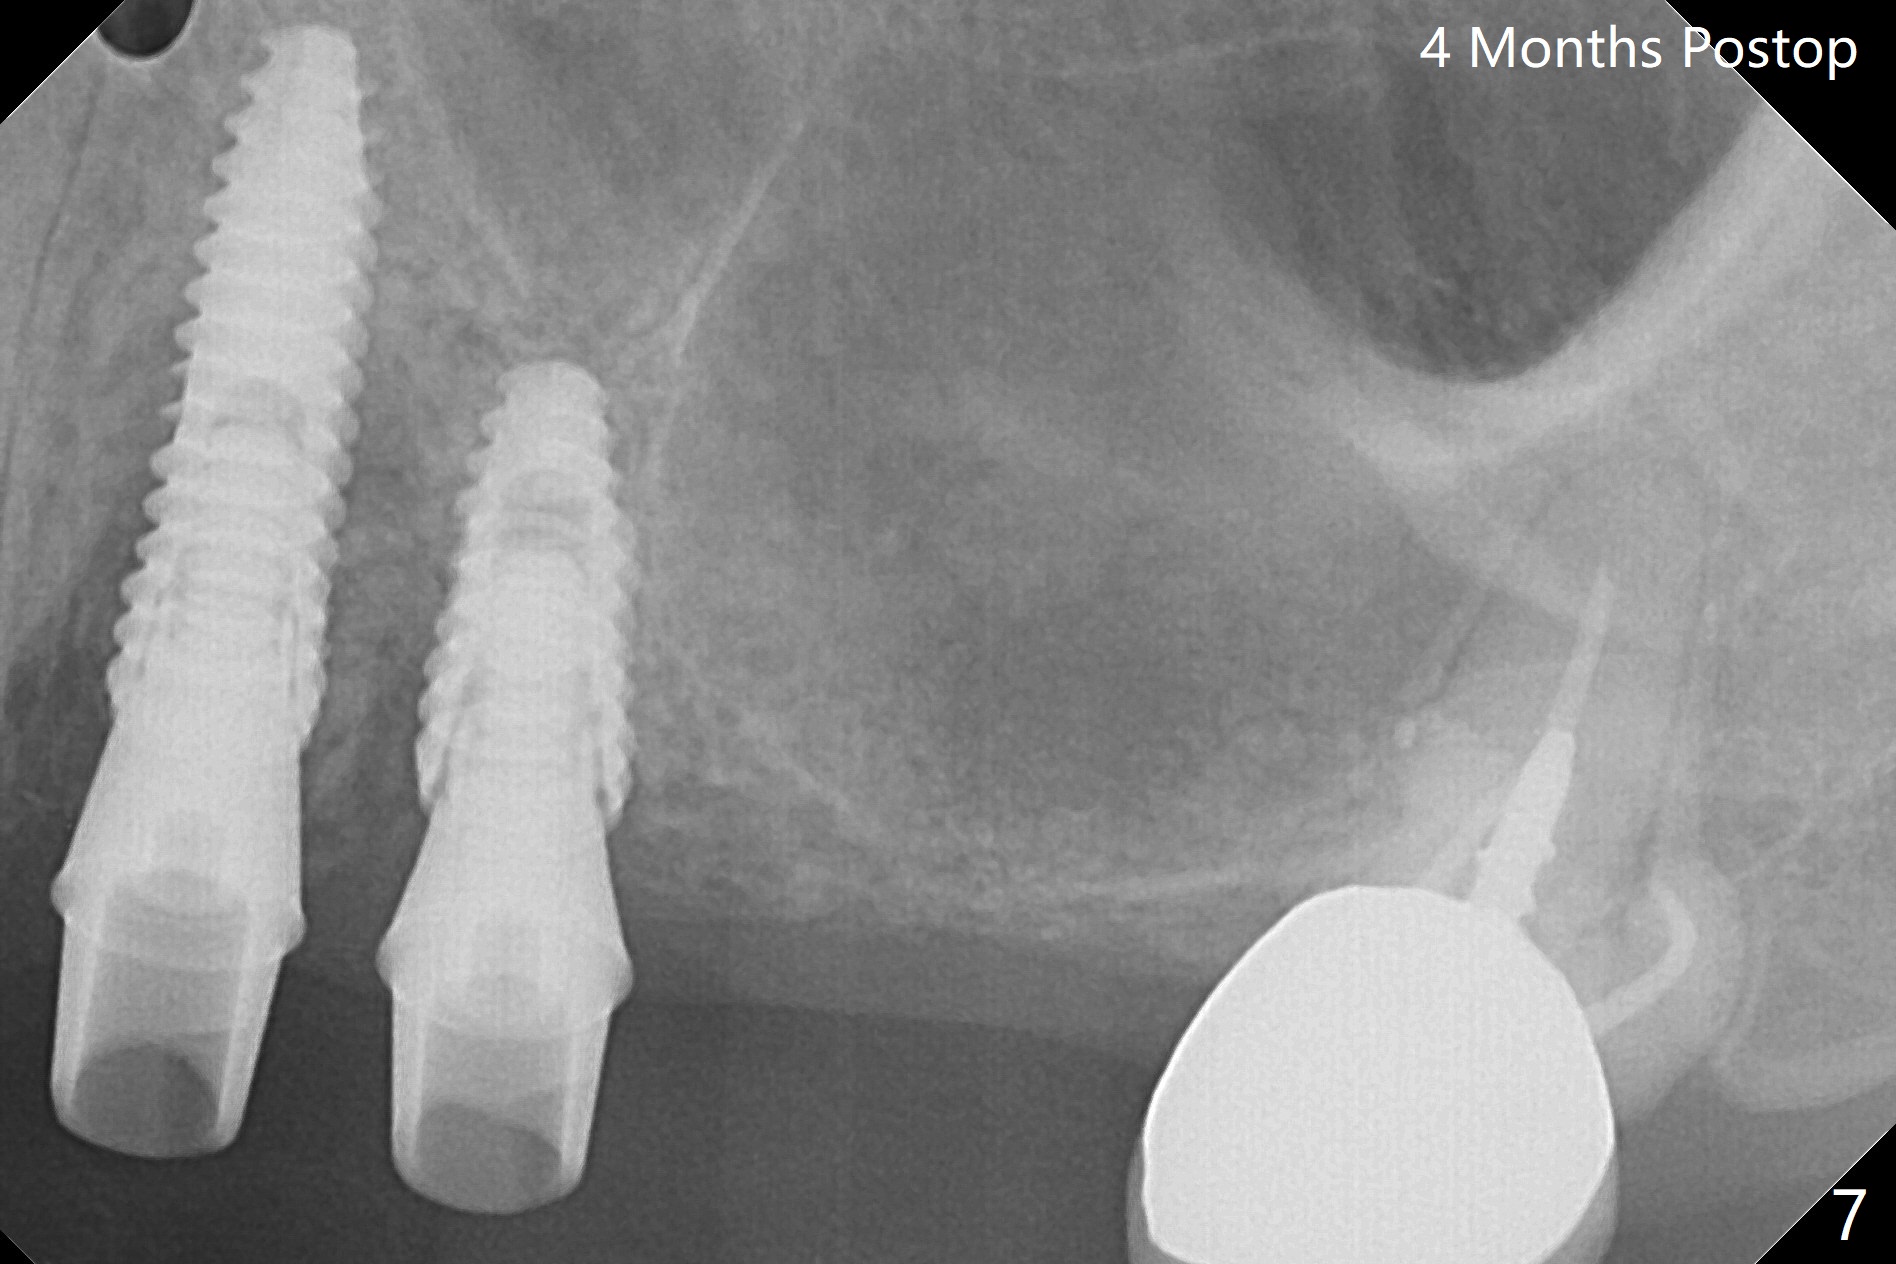

Osteotomy at #3 is performed last (Fig.1,2); as planned, a 4 mm cortical tap is used with guide for sinus lift. Unfortunately the sinus membrane is perforated. Implant placement is aborted. Instead Osteogen plug is inserted into the osteotomy, which is fixed in place by acrylic extending from the provisional at #4. Osteotomy for #3 implant will be attempted with control of the depth in 4 months. The patient has allergy to Amoxicillin (rash). When switching to Clindamycin, she develops diarrhea and loses 10 pounds. There is no abnormality at the site of #3 or 4 nearly 3 months postop (Fig.3). The next surgery will be most likely conducted without antibiotic 4 months postop. Try to draw blood for PRF. Take PA for #12 and 13 for possible impression. Remove the 3 temporary crowns, seat the guide across the arch and use no-stop fixture mounts at #4, and possibly 12 and 13. Follow the original drill sequence (check perforation after each drill, Fig.11) and use DIONavi sinus approach kit. Also load an appropriate stop for the round bur for sinus lift before hand. Mixture allograft with Metronidazole and PRF. In fact everything goes on as smoothly as planned. Osteotomy at #3 is underprep (3.5 mm in diameter drill instead of 4.0). The sinus floor appears to remain to be absent; 3.2 mm round bur is used for lift, alternating with water pumping. Following insertion of 3 pieces of PRF membranes and Vanilla Graft (Fig.4 *), a 4x10 mm dummy implant is placed. After additional bone graft (Fig.5 *), a final 4.5x7.3 mm implant is placed ~10 Ncm. The implant is placed deeper ~ 1 mm, followed by a 5.5x3 mm healing abutment (Fig.6). The implants at #12 and 13 seem to have osteointegrated (Fig.7). Impression is taken for #4, 12 and 13 with limited vertical space (Fig.8,9). An implant at #14 is being considered. There is faint bone graft around the apex of the implant 4 months postop (Fig.10). The implant sustains 25-30 Ncm torque when a 5.2x4(3) mm cemented abutment is placed. A permanent crown is cemented nearly 5 months postop (Fig.11). For the best cosmetic and masticating results, the occlusal surface should have certain degree of morphology, such as the buccal cusps (Fig.12 white curved lines). The abutment at #3 is placed and torqued to 30 Ncm before re-cementation of the repaired crown (increased occlusal surface contact). In fact the abutment at #4 is incompletely seated with a gap (Fig.13 <). The composite at #5 is dislodged while #3 crown is being repaired (*). The abutment at #4 is loose >1 year post cementation. The abutment remains incompletely seated (gap and longer apical space (double arrows)) when the abutment/crown complex rotates lingual mesiobuccal (Fig.14 curved arrow). Further proximal reduction and lingual rotation distobuccal leads to complete seating (Fig.15). It appears that incomplete seating at #13 is associated with hex mismatch (Fig.16, large apical space), which will be fixed next visit. One week later, the crown and abutment of #4 are seated together after crown repair (Fig.17). Since the abutment margin is subgingival, the crown is cemented, removed with abutment for residual cement removal and reseated with the abutment with torque at 30 Ncm. After this, the crown and abutment of #13 is reseated after mesiobuccal surface is trimmed (Fig.18), followed by pick up impression. A few days later, the crown/abutment are inserted together smoothly, the former cemented and the complex unscrewed for residual cement removal and last torqued at 30 Ncm without any X-ray confirmation.